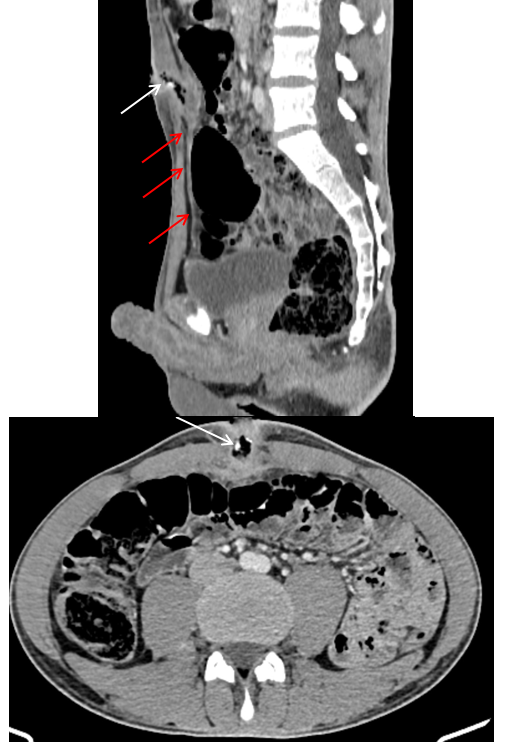

A 40-year-old man, with no relevant medical history, presented with persistent fever for three days, abdominal pain and purulent umbilical discharge, without associated digestive or urinary symptoms. On physical examination, the patient had an initial temperature of 38.9°C, purulent umbilical discharge with erythema and a tender umbilical masse Figure 1. Laboratory tests showed a significant leucocytosis at 16,000/mm3 and elevated C-reactive protein (122 mg/L), while urine analysis and renal function were within normal. Culture of the umbilical discharge revealed the presence of Klebsiella pneumoniae, while blood culture was negative. Abdominal ultrasound showed an echogenic retro-umbilical collection, and computed tomography confirmed the diagnosis of infected urachal sinus, heterogeneous collection, stone formation and gas comminated with the umbilicus Figure 2. The patient was initially treated with broad-spectrum intravenous antibiotics. Subsequently, a complete excision of the fistulous tract en bloc of the urachus with creation of a bladder cuff was performed Figure 3. The postoperative course was uneventful, and histological examination revealed no signs of malignancy.

Figure 2 Enhanced abdominal CT scan, in sagittal and axial views, showing a well-defined tubular collection, along the midline, with regular contours, and thick walls. It contains calcifications and air. The collection is a non-communicating dilatation of the urachus (red arrows) at the umbilical end, which is fistulised to the anterior abdominal wall. It measures 40 x 22 mm. The diagnosis was infected urachal sinus.